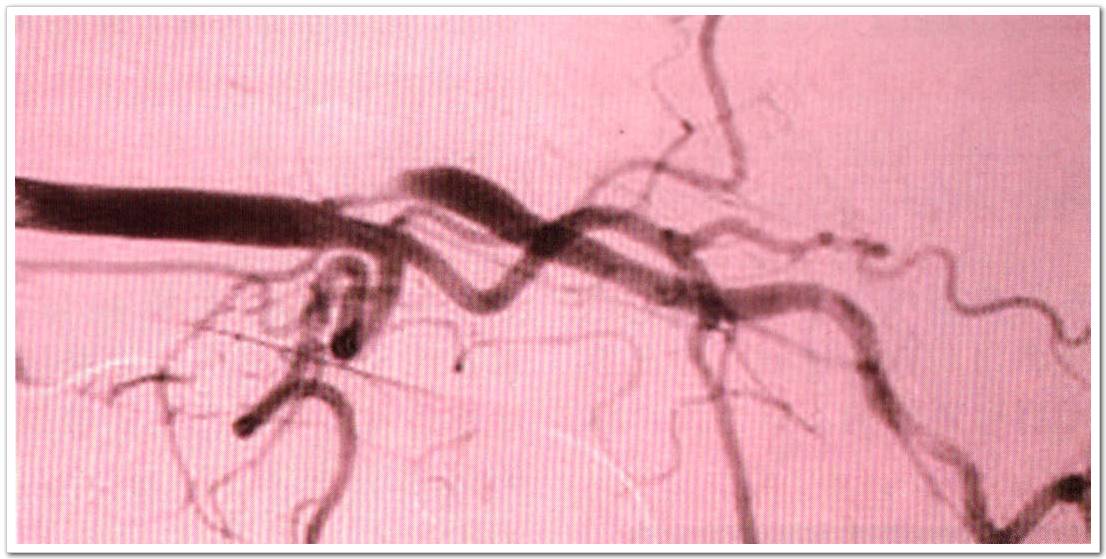

来自爱尔兰国家儿童中心神经内科的McCabe等人在此多中心观察性研究中,受试者为颈动脉狭窄≥50%的患者,受试者被分为无症状组(31例),early phase症状组(46例,缺血性卒中或TIA发作后4周之内)和late phase症状组(35例,缺恤性卒中或TIA发作后3个月以上),在late phase症状组中,23例患者已经接收了颈动脉介入手术,称为late phase介入组。对比无症状组、early phase症状组、late phase症状组患者的VWF:Ag及VWF:Ag II水平。对有症状的患者进行随访评估。TCD监测将患者分为MES阳性组或阴性组。